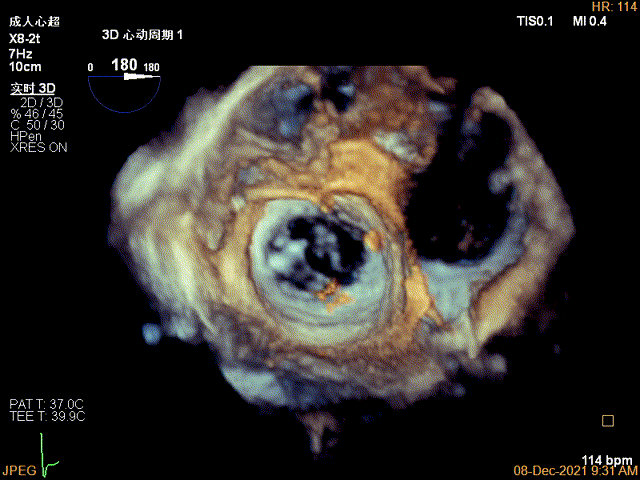

患者高龄、心衰时间较长、体型瘦小虚弱,无法耐受外科手术治疗,在门诊和入院初期评估时,由风湿性+功能性+退行性等多种原因导致的二尖瓣病变病理生理机制也给经导管介入治疗带来极大的挑战。门诊经胸超声心动图提示风湿性改变伴有轻度二尖瓣狭窄是传统意义上经导管缘对缘修复技术的禁忌,脱垂区后叶因AFMR参与被牵拉较短也是TEER的技术瓶颈。但患者反复心衰发作,病情恶化迅速,积极治疗重度的二尖瓣反流将是改善患者预后的一线生机。因此入院后我们通过经食道超声给这位患者进行了细致的评估后发现,患者的确有二尖瓣瓣叶增厚的改变,跨瓣压差在3-5mmHg,二尖瓣瓣口面积在4.43cm²,并没有明显的开放受限,瓣膜面积相对来说是TEER治疗的临界水平,后叶长度约7mm,尽管相对较短,在我们前期的TEER治疗患者中也可以达到充分的钳夹长度。因此经过心脏团队反复的综合评估,认为该患者有TEER治疗成功的机会,在充分药物治疗,患者心衰症状改善且病情平稳后,在患者以及家属强烈要求下,我们积极完善术前准备,择期行TEER治疗。

术前超声评估结果

术前超声诊断

Qlab软件勾画估测瓣口面积约:4.42cm²

二尖瓣口平均跨瓣压差:5mmHg